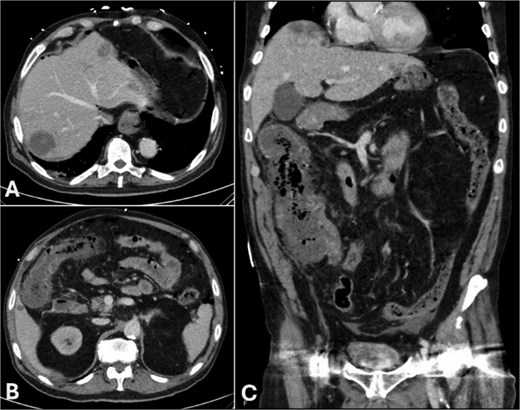

Non-contrast computed tomography (CT) of the abdomen demonstrated pneumoperitoneum and small volume free fluid in the pelvis and paracolic gutters, diffuse colonic wall thickening with mild stranding of the caecum, ascending and proximal transverse colon which also appeared relatively hypo-enhancing, and several irregular low-density foci within the liver, the largest in segment 7/8 measuring 83 × 47 × 30 mm (Fig. 1).

CT of the abdomen in portal venous phase: (A) subdiaphragmatic free gas and intra-hepatic hypodensities, (B) thickened hepatic flexure with hypo-enhancement, (C) thickened caecum and ascending colon with hypo-enhancement and surrounding stranding.